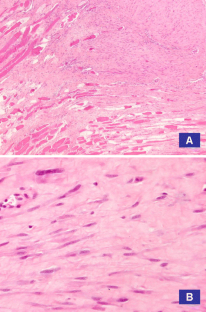

Fig. 1

Fig. 2

Fig. 3

Fig. 4

Fig. 5

Fig. 6

Fig. 7

Fig. 8

Fig. 9

Fig. 10

Fig. 11

Fig. 12

Fig. 13

Fig. 14

Fig. 15

Fig. 16

Fig. 17